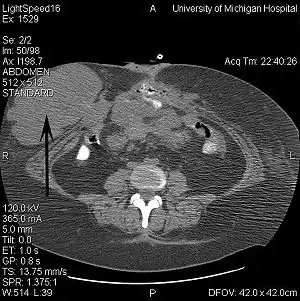

![]() КТ-знімок органів черевної порожнини у пацієнта з синдромом Гарднера та місцево-розповсюдженим десмоїдом (стрілка). КТ-знімок органів черевної порожнини у пацієнта з синдромом Гарднера та місцево-розповсюдженим десмоїдом (стрілка). | |